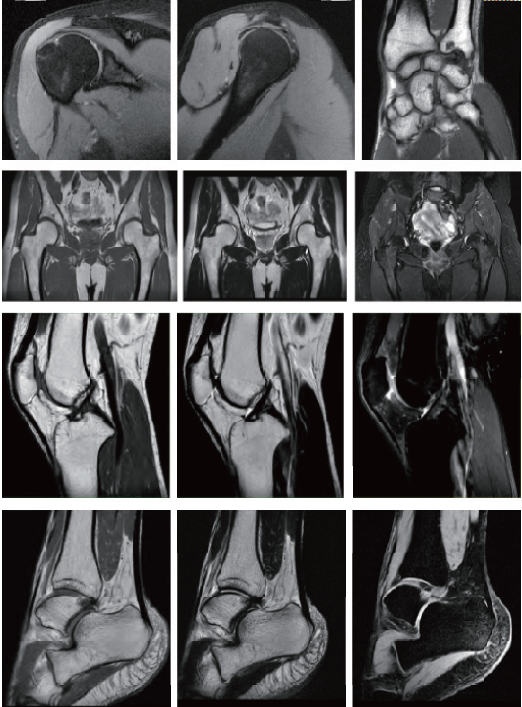

Uygulama Görüntüleri